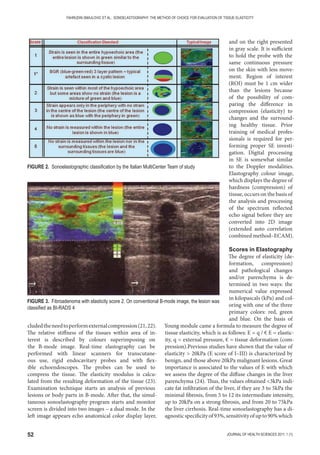

recovery pattern with the extent of canal compromise.

Like other bones, vertebral fractures are also undergo-

ing significant remodeling, so that the size and shape of

the spinal canal improves with time. However, this re-

modeling has no impact on neurological recovery (10).

Regarding the presence of fractures due to seasons, we

can see that the most common fractures appear in the

period of spring and winter. This phenomenon can be